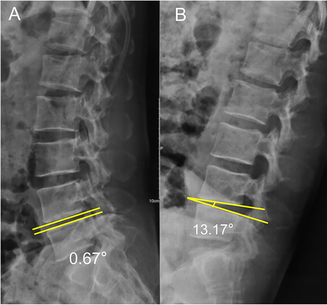

일반적으로 시상면(Sagittal) 영상에서 각운동이 10도 이상, 전위가 4mm 이상일 때 불안정성이 있다고 보게 됩니다.

예를 들면 아래 사진에서는 척추를 과신전(A)시켰을 때와 굴곡(B)시켰을 때 척추체 사이 각(Intervertebral space angulation)이 10도 이상이기 때문에 lumbar instability 에 합당한 소견입니다.

이렇듯 요추불안정성이 동반된 전방전위증의 경우에는 대부분 척추유합술이 필요하게 됩니다.